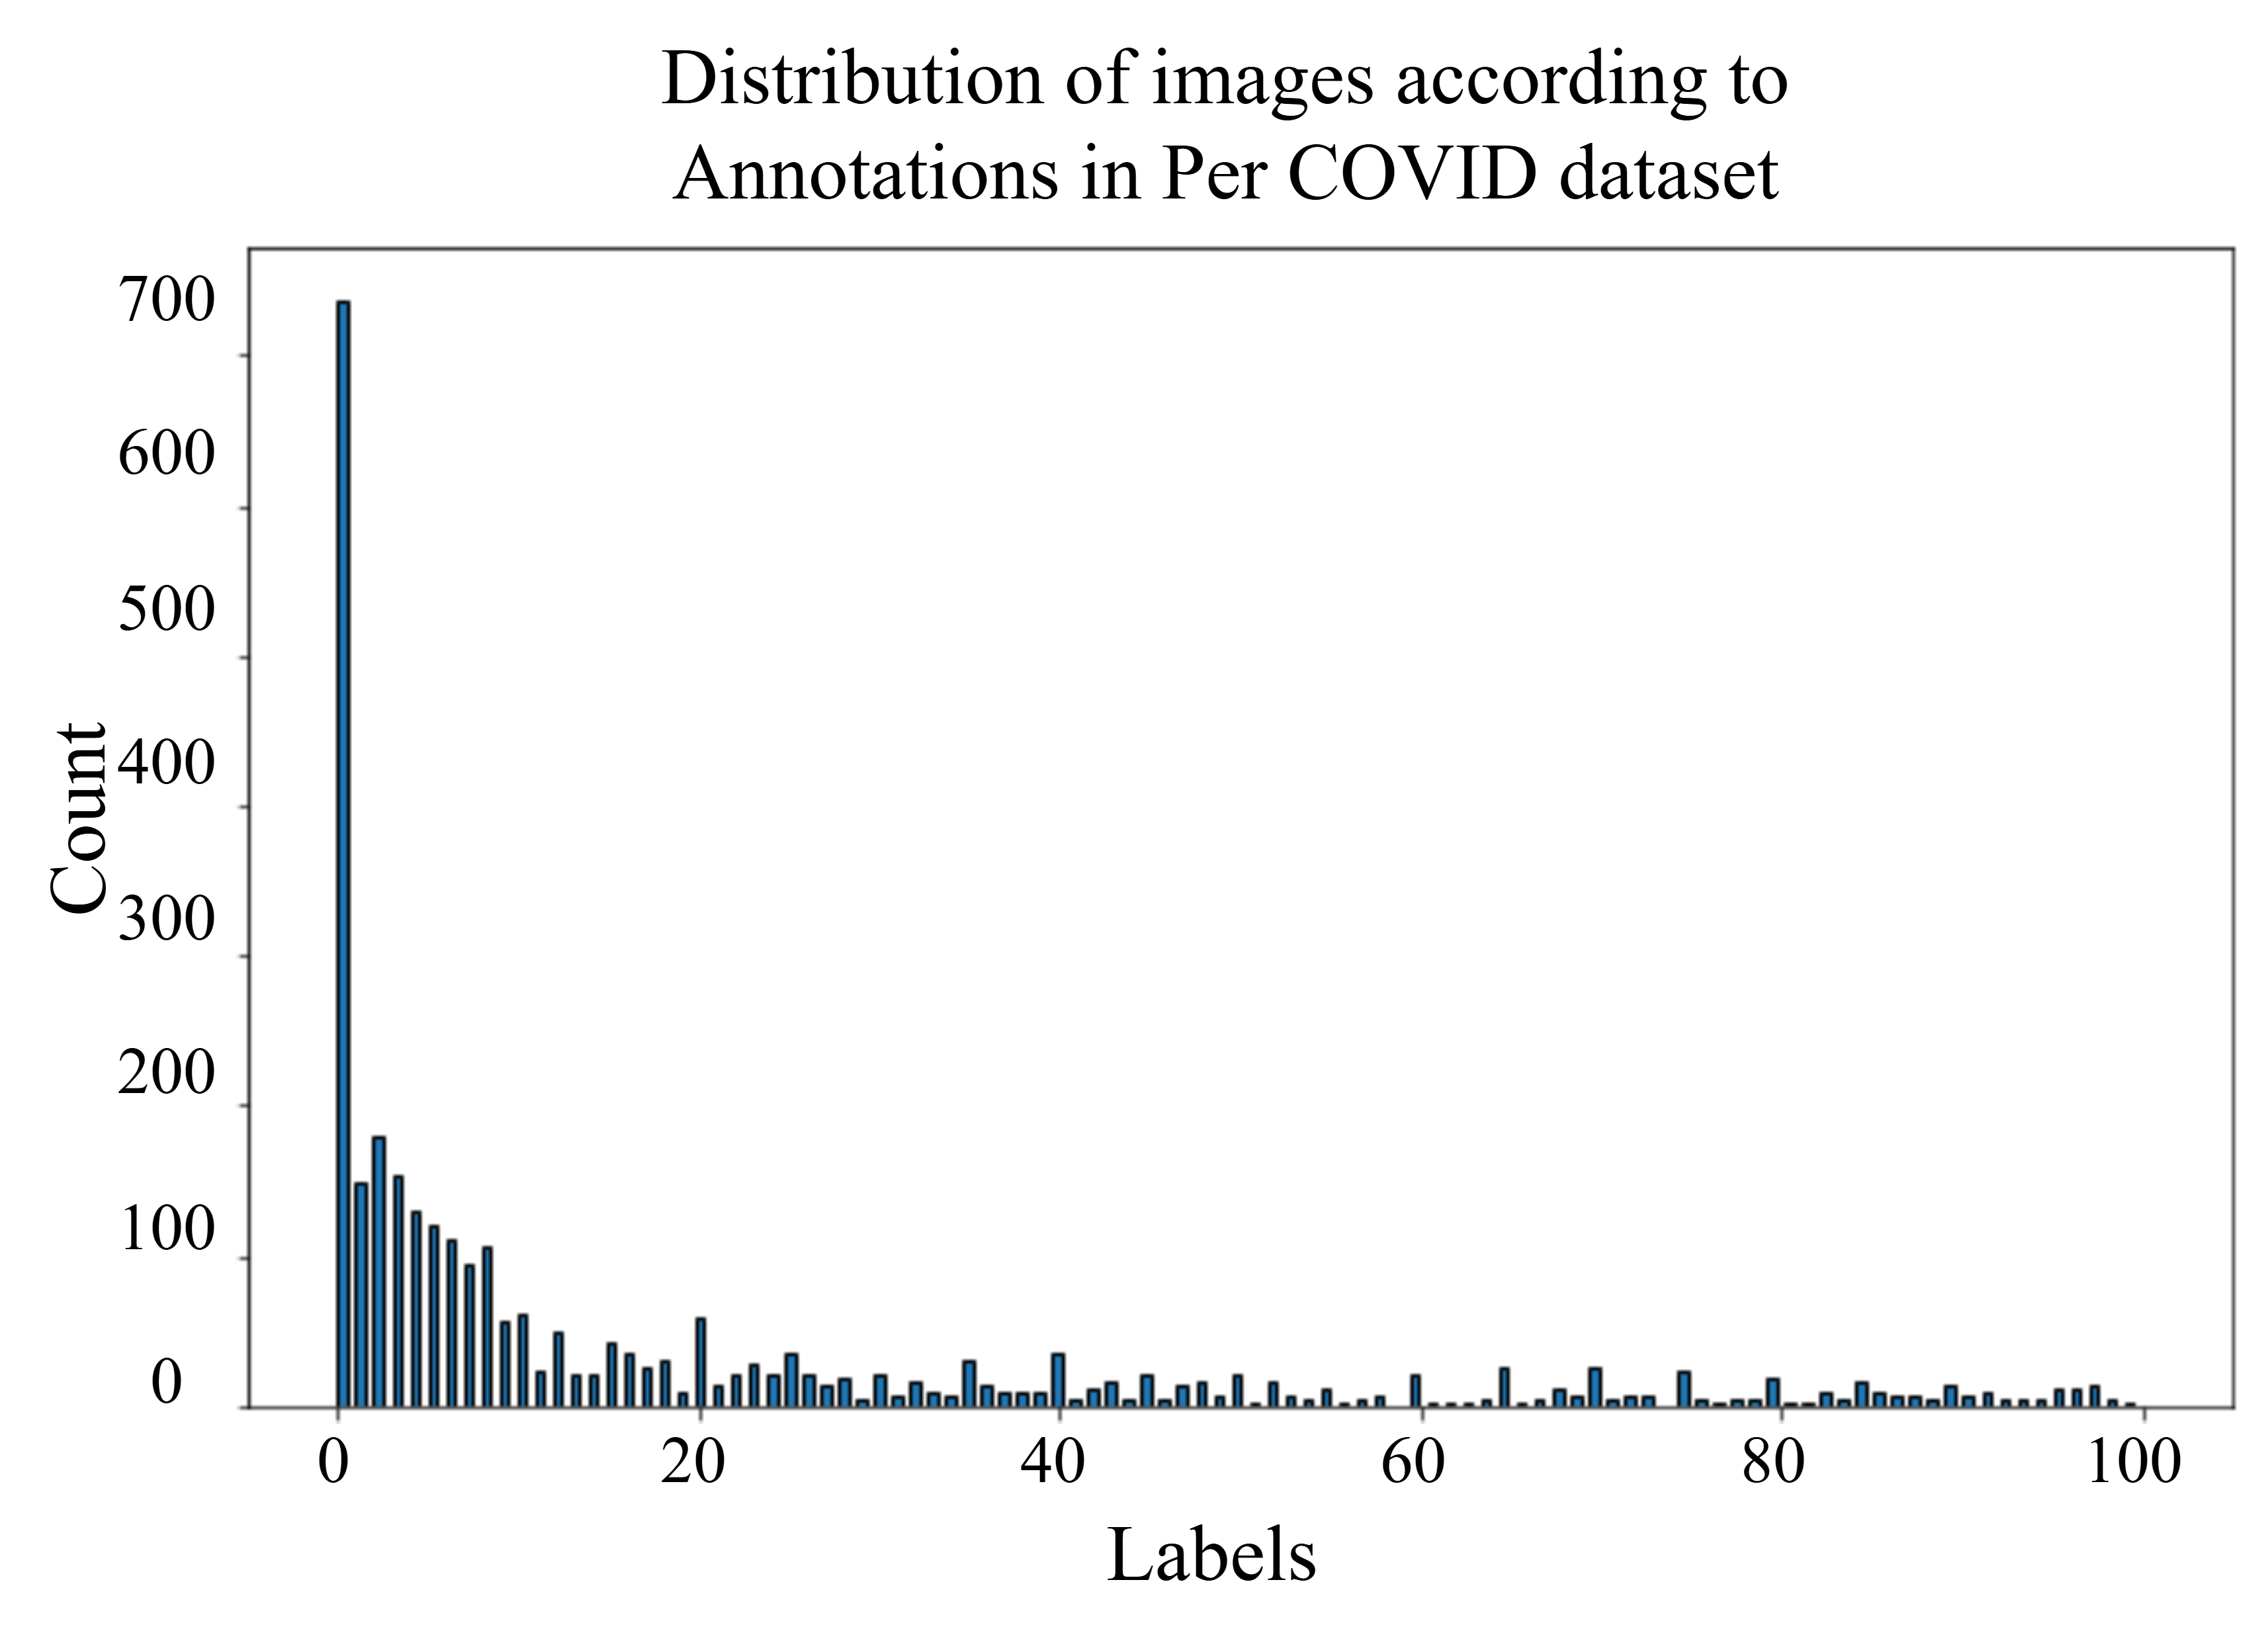

The Per-COVID-19 dataset’s training and validation splits were derived from 189 CT scans, each confirming a COVID-19 infection [8, 50]. The patient demographics include both males and females, aged between 27 and 70 years. Importantly, each CT scan in the Per-COVID-19 dataset corresponds to a single patient, ensuring that the number of scans matches the number of patients. COVID-19 diagnosis in this dataset is based on a positive reverse transcription polymerase chain reaction (RT-PCR) test and findings from CT scans, which two experienced thoracic radiologists carefully interpreted. Each CT scan comprises 40–70 slices, and the radiologists determined the percentage of lung area affected by COVID-19 infection relative to the total lung area. These COVID-19 Infection Percentage (CIP) annotations are expressed as percentages between 0% and 100%. The dataset is divided into 3,054 training slices and 1,301 validation slices [8, 50]. The testing split of Per-COVID-19 combines three different COVID-19 segmentation datasets [8]. For the test data, the ground truth for CIP is calculated by determining the proportion of infected pixels relative to the total number of lung pixels, using both the infection and lung segmentation masks. Producing accurate CIP compared with the ones of training and validation data. The Per-COVID-19 dataset presents additional challenges beyond typical CIP estimation from CT scans. Specifically, the challenge arises from training models with noisy labeled data, as the CIP ground truth for both the training and validation sets was estimated by radiologists on a scale of 100. Additionally, the research addresses domain adaptation issues, as the testing data originates from three sources different from those of the training data [7]. Figure 5 shows the distribution of the training data used in our paper.

On the other hand, Figure 5 shows the distribution of scores for CT scans within the range of 0 to 100, revealing that images with a score greater than 10 are less frequent. This indicates that the majority of the dataset consists of images with a score of 0, while those with non-zero scores are comparatively rare. This imbalance highlights the need for careful consideration during model training to ensure that cases with non-zero scores are adequately represented for reliable performance across the full range of scores which is achieved by data augmentation. Moreover, to consider the generalizability of our model in assessing lung disease severity, we tested its performance on CT images. Using the Per-COVID-19 dataset, which comprises 3,054 images, we trained our proposed model to predict the severity score represented by a scalar that ranges from 0 to 100. During training, conditional online score-correlated TransMix augmentation was applied to balance the dataset according to the strategy stated in Section 3.2.